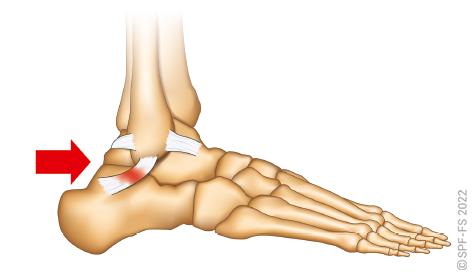

Les membres inférieurs

Les membres inférieurs sont chacun formés de trois segments :

Figure 2-13 : le membre inférieur

La hanche est l'articulation qui relie la cuisse au bassin. Le genou relie la cuisse à la jambe et la cheville la jambe au pied.

Ce dernier comporte cinq orteils numérotés de 1 à 5 de l'intérieur vers l'extérieur. Les phalanges sont numérotées de P1 à P3, dans le sens allant du talon vers l'ongle.